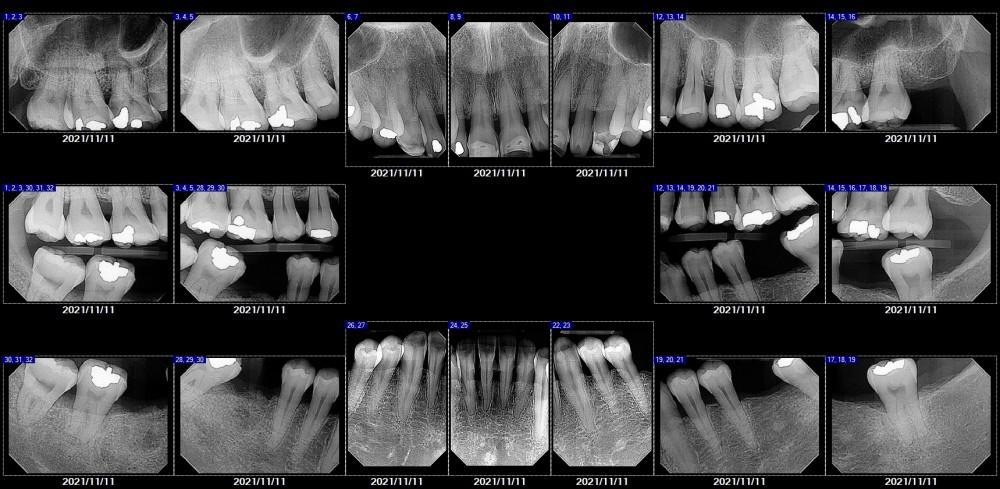

A young mom with tetracycline-stained teeth presents to Prosthodontist Qing asking for help. During our initial thorough and comprehensive exam, we noticed that besides the patient's major concern "smile", there is another major issue is her Periodontitis ( gum disease), which caused gum bleeding, tooth mobility, collapsed bite, and tooth shifting (Fig 1 and 2).